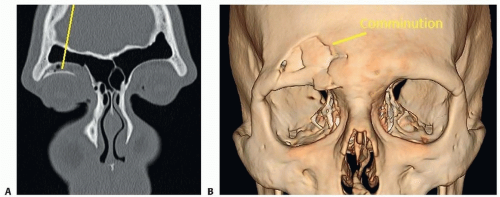

Standard of care imaging modality: thin-slice (1 mm) computed tomography (CT) scan1:

Axial, coronal, and sagittal views essential to provide complete assessment of degree of displacement and impact on surrounding structure.

3D views not essential, but can be helpful in badly displaced/comminuted fractures, especially if utilizing a limited access approach

Magnetic resonance imaging (MRI): impractical as it is an insensitive exam of the bone and some foreign objects; contraindicated in situations where metallic foreign objects (bullet fragments) may be present in soft tissues (FIG 2).